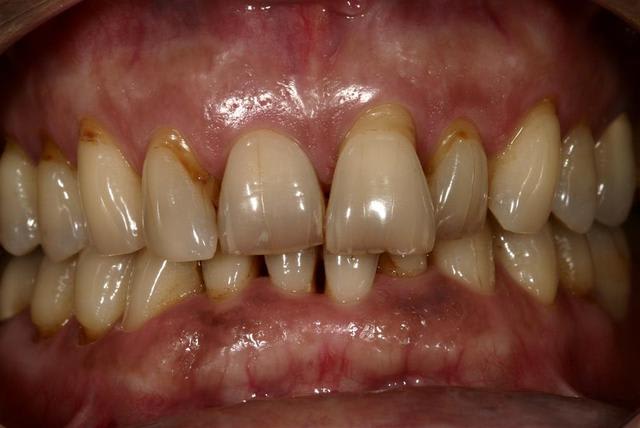

Le problème à traiter est la 12 qui migre suite au problème paro.

Cette jeune femme a 35 ans, elle va perdre cette dent si on n’intervient pas.

Je n’ai pas l’intention de traiter son endo ni sa classe II dentaire à gauche ni la linguoclusie de sa 16… Elle n’est pas demandeuse et son praticien traitant non plus.

- Quelle est l’étiologie, qu’est-ce qui s’est passé ? Un problème paro a permis la migration des dents.

- Quels sont les mouvements à réaliser ? De simples mouvements de version pour redresser les dents et fermer les diastèmes..

Les cas de migrations dentaires dus à un problème paro sont vraiment les cas types pour ce genre de traitement

Ce sont des traitements simples que tout chirurgien-dentiste est capable de réaliser.

Après de nombreux échanges avec Dancha, j'ai mis en route ce cas.

On part de loin, on se bat encore pour l'hygiène mais on avance.